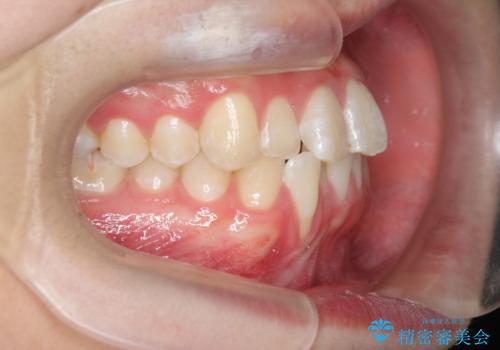

クロスバイト・歯並びが原因の歯肉退縮歯、矯正治療による審美性の改善

- 前歯の歯並び、下顎前歯の歯ぐきの下がり(歯肉退縮)の改善を求めて来院されました。

歯肉退縮の根本的な原因はすれ違った噛み合わせによる為害性のある咬合状態にあるため、歯肉退縮に対し結合組織の移植術を行うのではなく当該歯を抜去し部分矯正を含めた治療計画を立案します。

矯正治療を行ったことで、噛み合わせが安定し審美性も機能性も向上することができました。